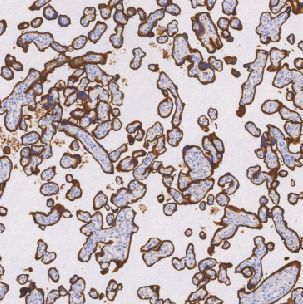

CD71鼠抗人CD71单克隆抗体

CD71分子是II型膜糖蛋白分子量大约为180KD。CD71被认为是铁传递蛋白受体并由两个二硫化物组合的90KD亚单位组成。CD71分子在细胞增生中通过控制铁的提供起关键作用,这是许多代谢旁路的基础组成,通过结合与细胞内吞噬铁转运蛋白,主要是铁携带蛋白。据报道CD71蛋白表达在活化B细胞和T细胞,巨噬细胞增生细胞和代谢活跃的细胞如神经元中。

- 阳性部位:胞质,胞膜

- 适用组织:石蜡切片

- 预处理:热修复